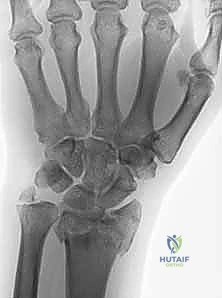

- الأشعة السينية (X-rays): بأوضاع متعددة لتقييم زوايا الكسر ومقدار الانهيار العظمي.

- الأشعة المقطعية (CT Scan) مع إعادة البناء ثلاثي الأبعاد (3D Reconstruction): وهي خطوة إلزامية في الكسور المعقدة. تتيح للدكتور هطيف رؤية كل شظية عظمية داخل المفصل بدقة متناهية والتخطيط للعملية الجراحية قبل دخول غرفة العمليات.

لفهم قيمة "الصفيحة الجسرية"، يجب أن نقارنها بالبدائل المتاحة. في حالات التفتت الشديد (حيث يكون العظم أشبه بالزجاج المهشم)، تفشل العديد من الطرق التقليدية.

كسور عظم الكعبرة البعيد، خاصة تلك الناتجة عن حوادث قوية أو سقوط من ارتفاعات عالية، تمثل تحديًا طبيًا وجراحيًا كبيرًا. هذه الكسور تختلف تمامًا عن كسور الرسغ البسيطة التي قد تحدث نتيجة تعثر بسيط. في حالات الطاقة العالية، غالبًا ما تتسبب القوة الميكانيكية الهائلة في تهشم العظم وتفتته إلى قطع صغيرة (Comminution)، وتؤثر بشكل مباشر ومدمر على سطح المفصل الحساس (Intra-articular fractures).

الميكانيكا الحيوية للإصابة (Biomechanics of Injury)

في حوادث الطاقة العالية (مثل حوادث الدراجات النارية أو السقوط من السقالات)، يتم دفع عظام اليد بقوة هائلة داخل عظم الكعبرة، مما يؤدي إلى "انفجار" العظم من الداخل وتفتته (Pilon-type fractures). هذا التفتت يجعل العظم غير قادر على تحمل أي ضغط، وينهار على نفسه (Collapse).